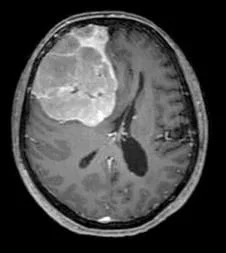

Un méningiome peut être diagnostiqué au scanner où il apparaît comme une masse ronde à la périphérie du cerveau, avec un épaississement de l’os au niveau de sa base d’insertion sur la méninge.

Il est plus fréquemment retrouvé sur une IRM sous forme d’une masse “blanche” après injection du produit de contraste intraveineux et entourée d’un œdème. Les méningiomes peuvent se rencontrer dans différentes localisations intra-crâniennes, plus ou moins facilement accessibles et qui conditionneront la technicité et les risques du geste qui vous sera proposé par votre chirurgien.

frontal droit